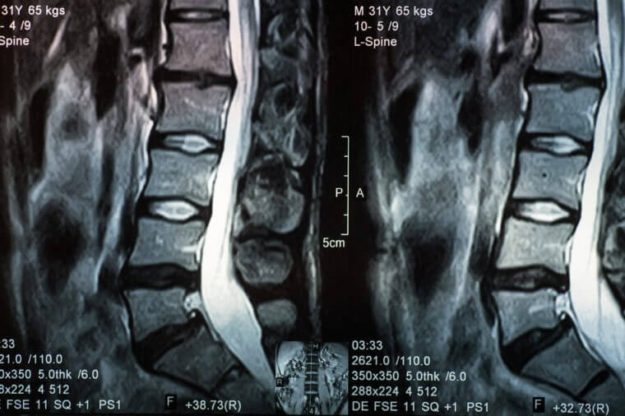

CUANDO UN PACIENTE TIENE CADERA Y DOLOR DE ESPALDA, ¿DE DÓNDE VIENE EL DOLOR? ¿DE LA CADERA? ¿DE LA COLUMNA BAJA? ¿DE AMBOS?

por Marc Darrow. En la Facultad de Medicina de la University of Washington, Departments of Orthopaedic Surgery and Neurology and Physical Therapy, los cirujanos y terapeutas querían examinar a los pacientes que tenían osteoartritis de cadera y/o deformidad de cadera para encontrar una relación con el dolor de espalda. El complejo espalda/ cadera…